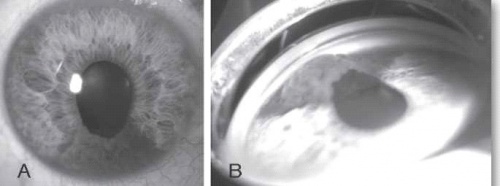

בבדיקה של החולה תתגלה מסה, לרוב מלנוטית, בענביה, שיכולה להיות ממוקמת אנטומית בחלק הקדמי של העין (בקשתית - Iris) או בחלקים האחוריים של העין (בגוף הסיליארי - Ciliary Body או בכורואיד - Choroid) (ראו צילומים 1 ו-2). גידולים גדולים יכולים לערב שני אזורים אנטומיים, ולעתים אף את כל השלושה.

מלנומה של הקשתית מהווה כ-5% מכלל המלנומות של הענביה, גידול זה נחשב פחות אגרסיבי ביולוגית. במעקב ארוך טווח נמצא שמלנומה של הקשתית נוטה לשלוח גרורות רק ב-3%, ב-5% וב-10% במעקב של חמש שנים, עשר שנים ועשרים שנה בהתאמה.[2]

מלנומה של הגוף הסיליארי היא לרוב א-סימפטומטית. גידול זה מהווה כ-10% מכלל המלנומות של הענביה. בשל מיקומו החבוי מאחורי הקשתית, הגילוי של המחלה נעשה בדרך כלל רק בשלבים מתקדמים. מלנומה של הגוף הסיליארי נחשבת לאגרסיבית מבין המלנומות של הענביה.